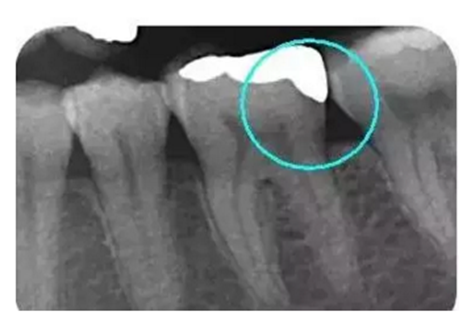

從下面這張X線中可以看出,嵌體遠中邊緣沒有懸突,與牙體邊緣密合相接。

5.png